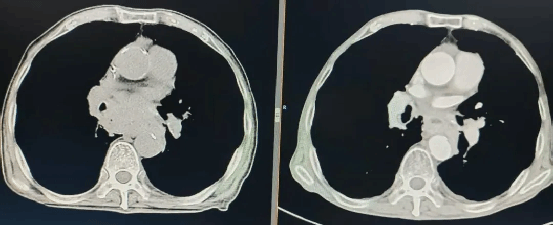

2025-11-0771岁老人主动脉夹层进急诊,血管介入科40分钟精准“拆弹”挽救生命

急诊铃响“心脏炸弹” 随时引爆“胸背像被刀割一样疼!” 11月5日,我院急诊科接入一名71岁男性患者,其血压飙升至 220/130mmHg,伴随大汗淋漓、濒死感。急诊科党妙杰医... -